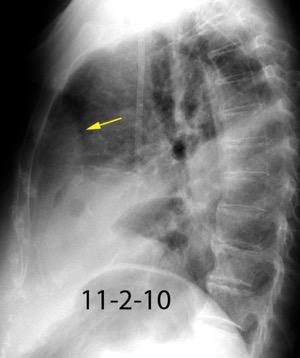

Absceso secundario a perforación de carcinoma. 3-4%. En flexura esplénica puede tener absceso subfrénico o empiema.

Empiema pleural secundario a carcinoma de la flexura esplénica (masa visible)

Lian R et al. Empyema caused by a colopleural fistula. Medicine (Baltimore) 2017/Osada T,, et al. Thoracic empyema associated with recurrent colon cancer: report of a case and review of the literature. Dis Colon Rectum 2001